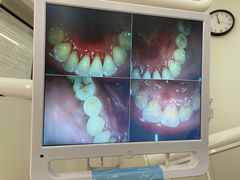

• 牙博士口腔品牌连锁(杨浦店)

• -牙博士口腔品牌连锁(杨浦店)

Ulquiorra | 21-01-12

报错